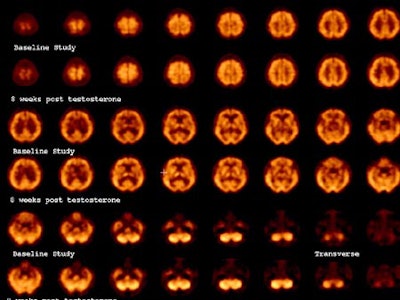

The SPECT study

"Our study sought to determine whether SPECT imaging could identify changes in cerebral perfusion as a result of testosterone therapy," Friedman said. "We designed the study in a longitudinal fashion, to see whether these changes are constant or whether they change with time."

The team enrolled 9 males, aged 58 to 72, with documented low testosterone levels of 29.5 ± 5.8 pg/ml free early morning testosterone levels (compared with normal levels of 50-210 pg/ml). The subjects had been referred by an endocrinologist, and candidates with a history of prostate cancer, benign prostate hypertrophy, or cerebrovascular disease were excluded.

All subjects underwent therapy with 200 ml of testosterone enanthate by intramuscular injection every two weeks. Each patient completed an ADAM (androgen deficiency in aging males) questionnaire before and after therapy.

SPECT studies were acquired with a triple-head gamma camera using UHR fanbeam collimation (120 steps @ 50 sec/step), following administration of 25 mCi of Tc-99m HMPAO. The images were processed by data rebinning, without attenuation correction, and using a Hanning filter with a cutoff of 0.9 cyc/cm. The data was converted to the Mayo Analyze format, and imported into SPM96 analysis software. The images were analyzed visually, and the readers were blinded to the results of the SPM analysis, Friedman said.

In all, 7 patients completed the study, which included baseline scanning followed by repeat scans at 3-5 weeks and 3-4 months.

Friedman also noted some limitations: that the number of subjects was small, and that intramuscular injection was used rather than a transdermal patch, which would have provided a steady state of testosterone. No placebo was used. And the researchers could not determine whether testosterone or its derivatives are the active agents behind the changes, which will be addressed in the next phase of the study, Friedman said.

"It is difficult to make the leap from perfusion imaging to a theoretical concept, but the animal evidence and the findings in our perfusion imaging study suggest that as a result of testosterone replacement we are seeing changes in the serotoninergic system, with activation of the serotoninergic nuclei in the midbrain and activations in cortex via the serotoninergic system," he wrote. "While I cannot prove this, perhaps researchers with access to sertonin transporter or receptor ligands can examine this in the future."